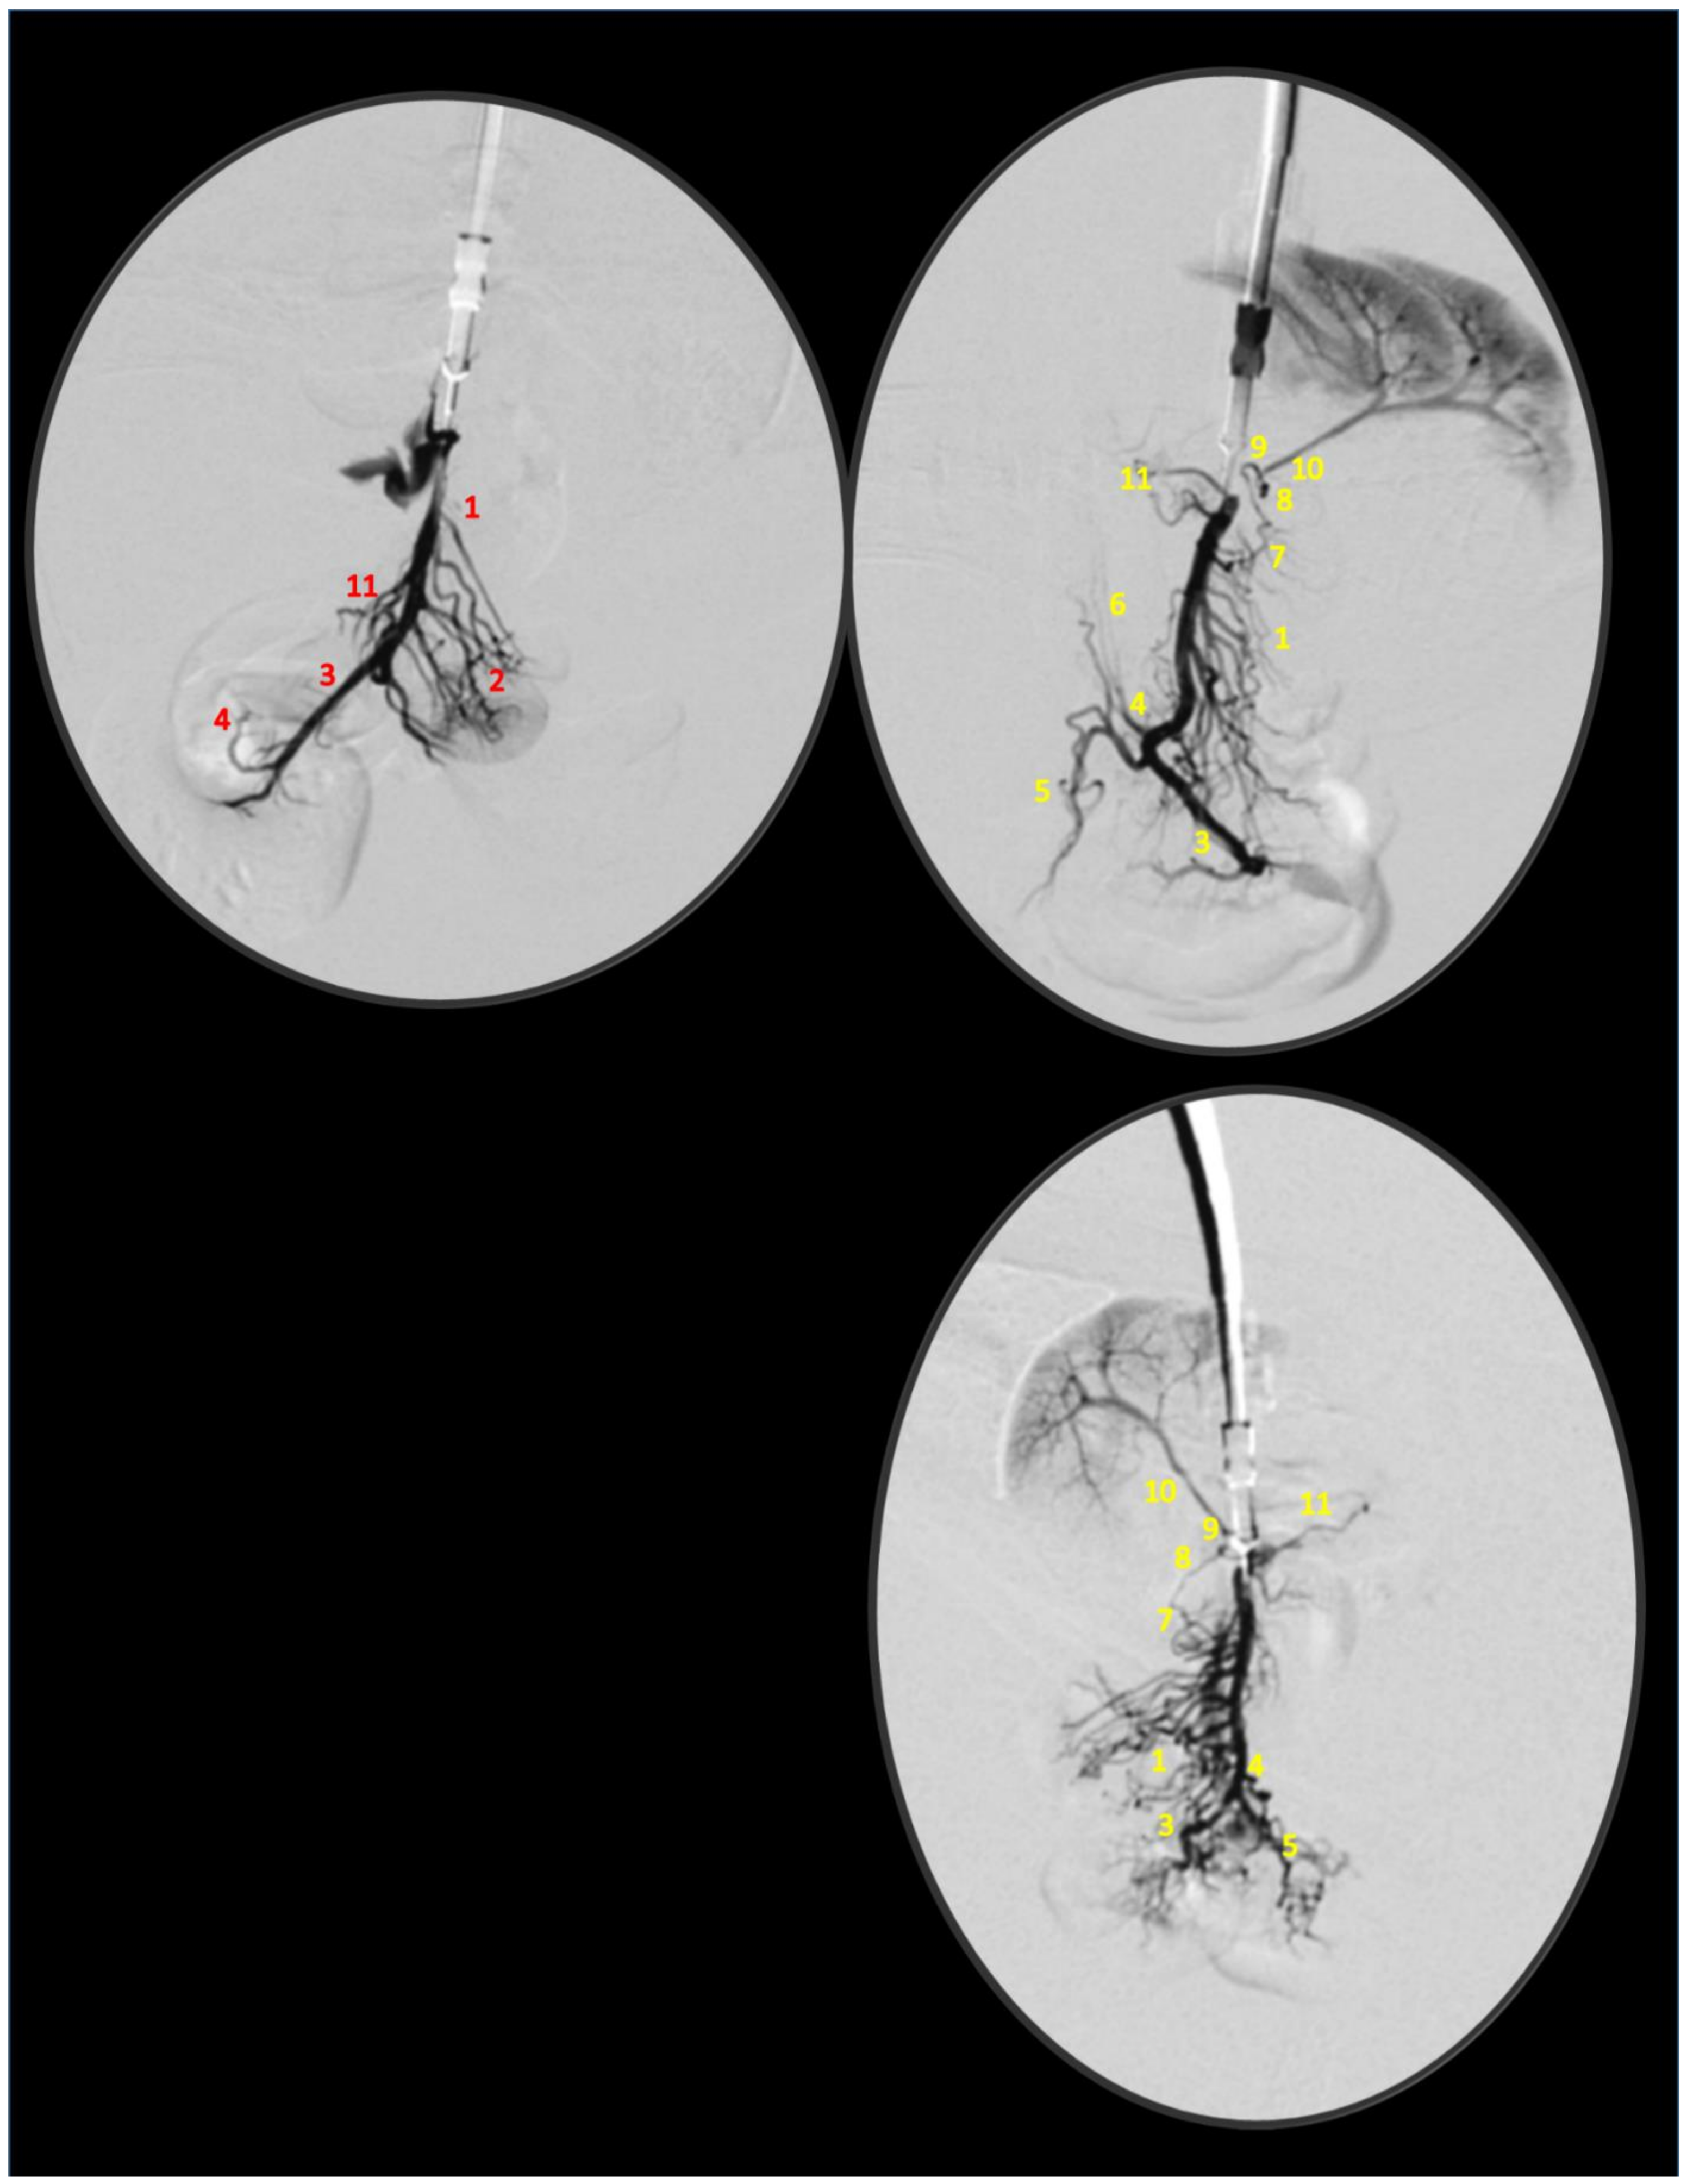

2.4. Venography